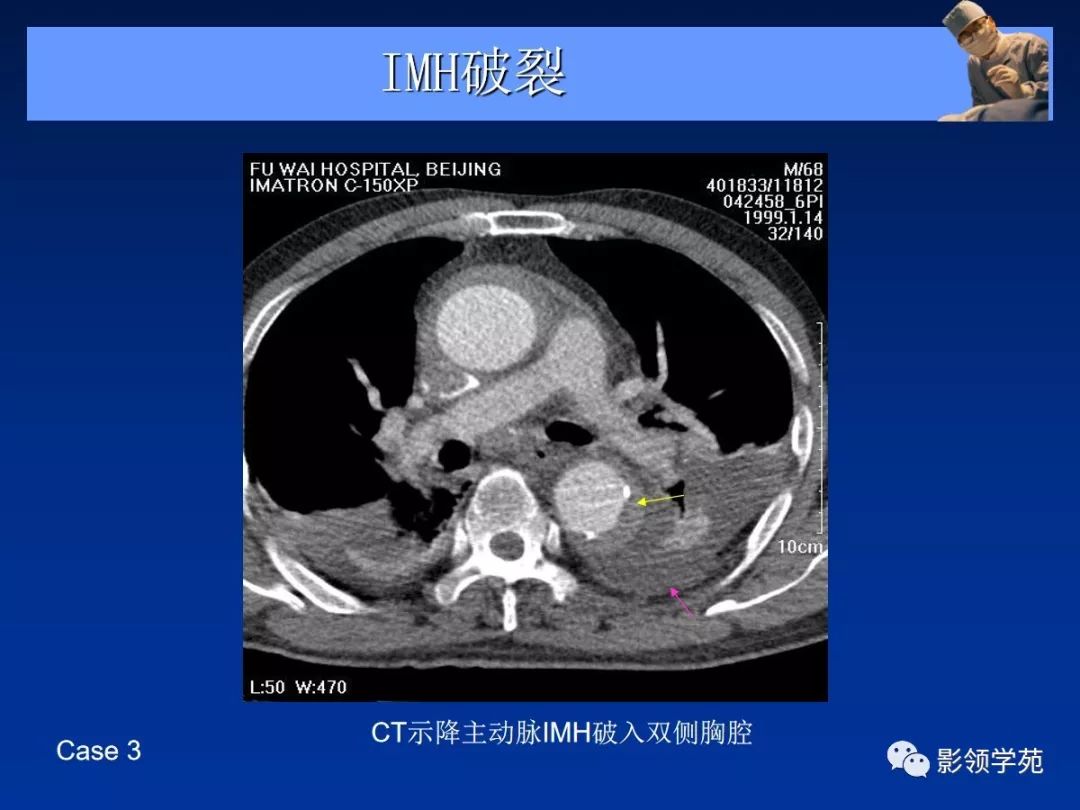

- 主动脉壁内血肿 ( intramural aortic hematoma, IMH)